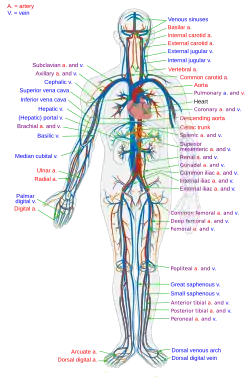

El colapso cardiovascular, colapso circulatorio o insuficiencia circulatoria es un término médico que se refiere a la incapacidad del sistema circulatorio de aportar sangre oxigenada a los tejidos del cuerpo para sus necesidades biológicas. Puede producirse de manera progresiva o crónica, así como puede ser un evento súbito, en cuyo caso se denomina insuficiencia circulatoria aguda.[1] Si bien los mecanismos, causas y síndromes clínicos son diferentes, la patogénesis es la misma: el sistema circulatorio falla en mantener el suministro de oxígeno y otros nutrientes a los tejidos y para eliminar el dióxido de carbono y otros metabolitos de ellos. El fallo puede ser hipovolémico, distributivo.

Un fallo generalizado es aquel que se produce en un amplio rango de lugares en el cuerpo, tales como choque sistémico después de la pérdida de una gran cantidad de sangre colapsando todos los sistemas circulatorios en las piernas. Una falla específica puede remontarse a un punto particular, tal como un coágulo.

Insuficiencia circulatoria central

El colapso circulatorio cardíaco afecta a los vasos del corazón, tales como la aorta y es casi siempre fatal. Se denomina en ocasiones insuficiencia circulatoria «aguda».

Insuficiencia circulatoria periférica

El colapso circulatorio periférico implica arterias periféricas y venas en el cuerpo y puede causar gangrena, fallo orgánico u otras complicaciones graves. Esta forma es a veces llamada insuficiencia vascular periférica, choque (o shock) o cierre vascular periférico.